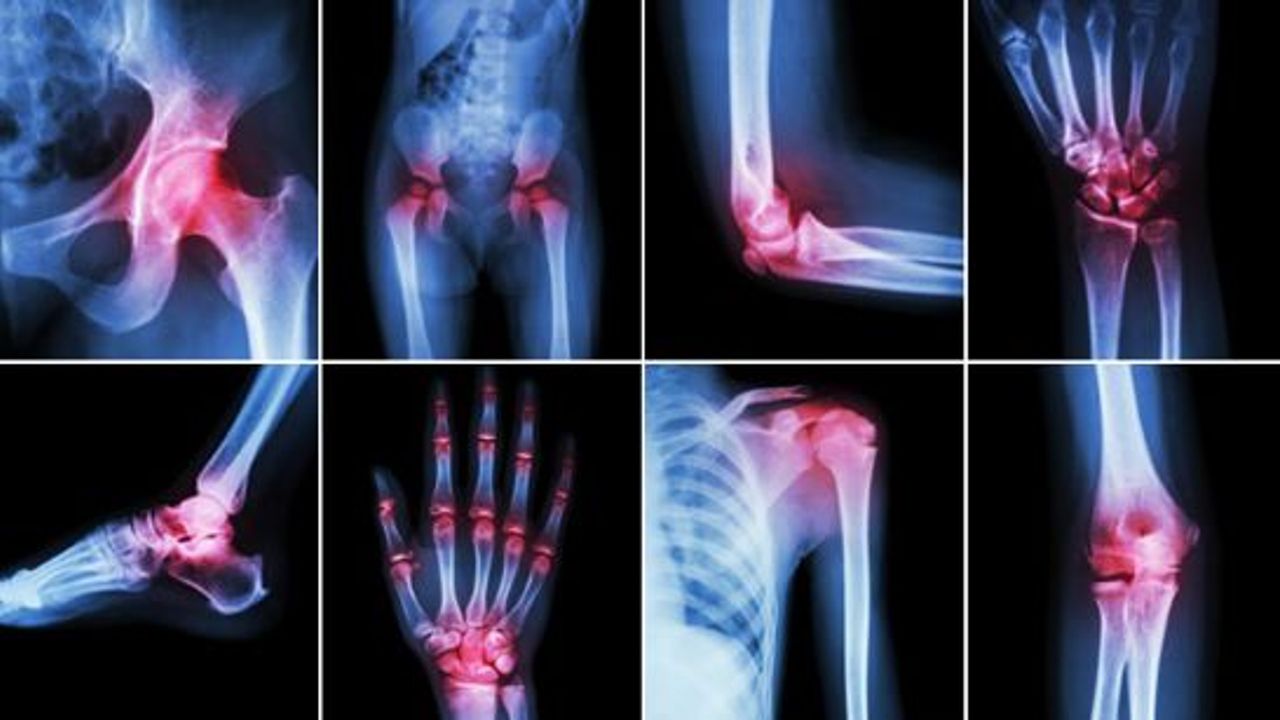

Eklemler vücudunuzun kemiklerinizin birleştiği kısımlardır. Eklemler iskeletinizin kemiklerinin hareket etmesini sağlar. Eklem ağrısı, eklemi çevreleyen bağ, bursa veya tendonların herhangi birini etkileyen yaralanma nedeniyle ortaya çıkabilir. Yaralanma ayrıca eklem içindeki bağları, kıkırdakları ve kemikleri de etkileyebilir. Ağrı ayrıca eklem iltihabı (romatoid artrit ve osteoartrit gibi artrit) ve enfeksiyonun bir özelliğidir ve nadiren eklem kanserine neden olabilir. Peki Eklem ağrıları neden olur?

Kilo sorunları, çeşitli spor aktiviteleri, kazalar, iltihaplanmalar gibi çeşitli hastalıkların eklem ağrısına yol açması mümkündür.

Kemik ağrıları ise kemik erimesi (osteoporoz) başta olmak üzere, ufak kırıklara, osteoid osteoma, enkondroma gibi tümör oluşumlarına bağlı olarak gelişebilir.

Kazalar, spor aktiviteleri, kilo fazlalığı (obezite) veya çeşitli hastalıklar eklemlerde ve kemiklerde ağrıya neden olurlar. Hareket için eklemlere ihtiyaç duyarız. Eklemlerde ağrı varsa nedenlerini bulup tedavi etmeliyiz. Örneğin;